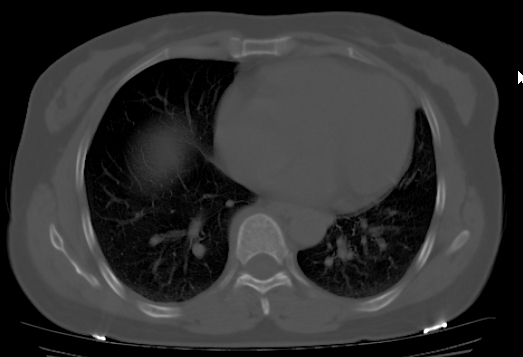

标题: CT25227:背部疼痛伴双侧胸壁痛2月,食欲差。 [打印本页]

标题: CT25227:背部疼痛伴双侧胸壁痛2月,食欲差。

肺结核并胸椎结核?请各位高手指教。

左肺结核灶,胸椎结核并冷脓肿。

支持!不排除骨原发淋巴瘤肺内转移。

食道癌并胸椎及肺内转移